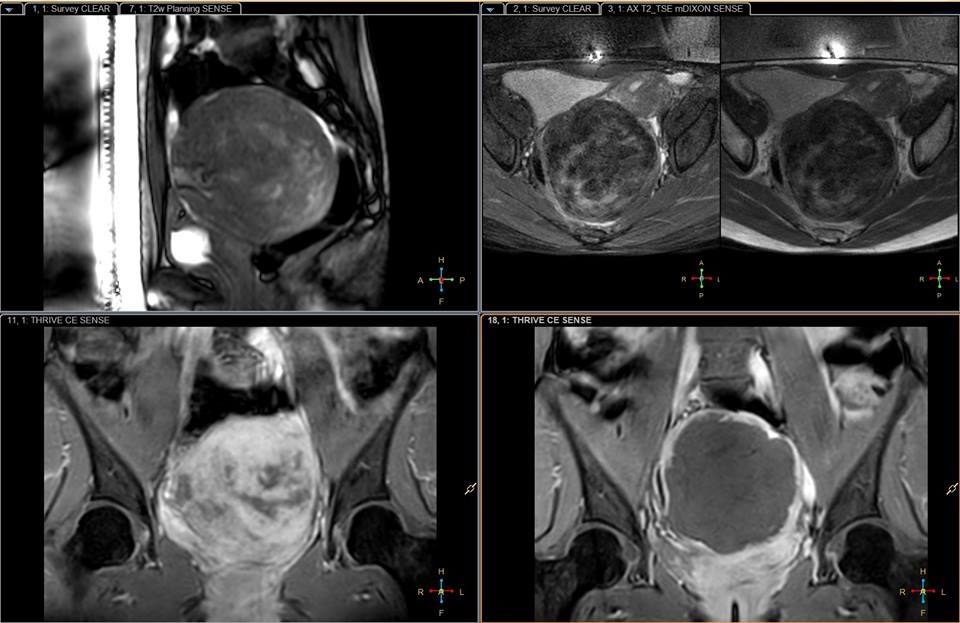

Tại đây, bác sĩ thông báo chị có một khối u xơ tử cung khoảng 100 mm, chiếm toàn bộ tử cung và phần bụng dưới. Các kết quả chụp chiếu cho thấy đây là u xơ tử cung trong cơ chiếm hoàn toàn vùng chậu. Kết quả siêu âm cũng ghi nhận chị đã bị thận ứ nước nặng độ 2 cả hai bên, suy giảm chức năng thận.

| Hình ảnh khối u của bệnh nhân H. Ảnh: Bác sĩ cung cấp. |